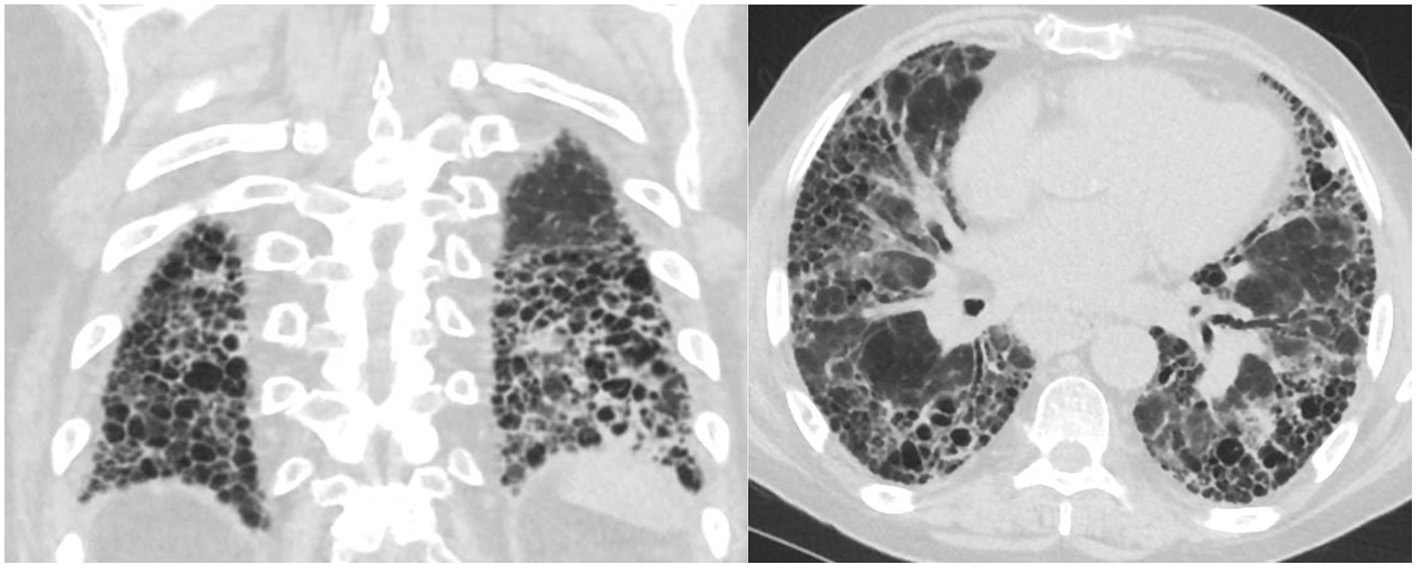

Not all patients with connective tissue disease have an NSIP pattern, some patients have a UIP pattern with exuberant honeycombing and the straight edge sign (Figure 2) which can also progress in extent over time (24).

Figure 2

Axial and coronal images with straight edge sign characteristic of a UIP pattern associated with CTD.